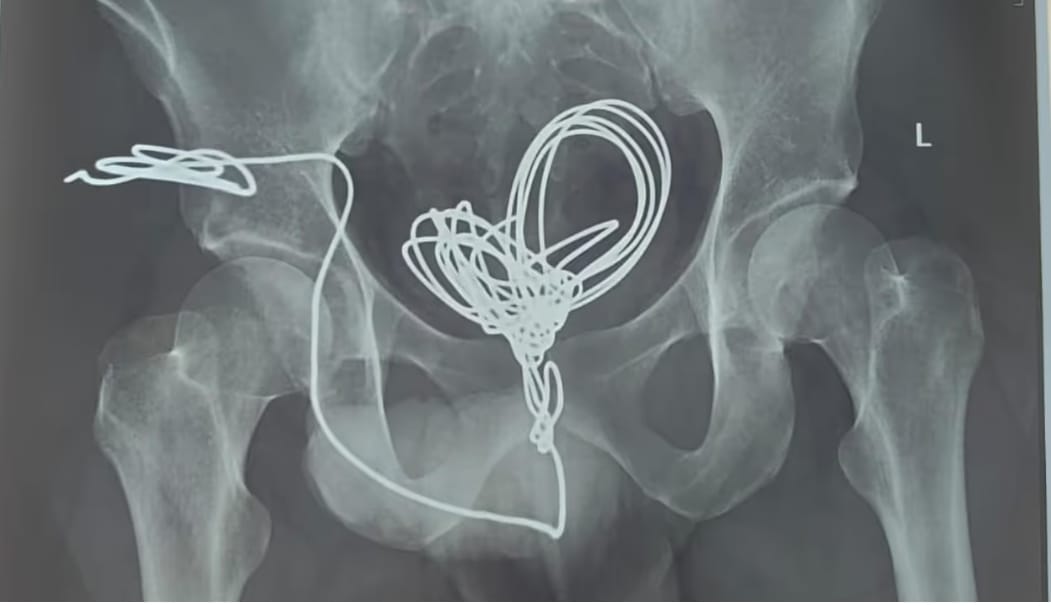

മൂത്രനാളിയിലേക്ക് യുവാവ് കുത്തിക്കയറ്റിയത് മൂന്ന് മീറ്ററോളം ഇലക്ട്രിക് വയർ; പുറത്തെടുത്തത് വയർ തുറന്നുള്ള ശസ്ത്രക്രിയയിലൂടെ

തിരുവനന്തപുരം മെഡിക്കൽ കോളജ് ആശുപത്രി യൂറോളജി വിഭാഗത്തിൽ വയർ തുറന്നു നടത്തിയ ശസ്ത്രക്രിയയിലൂടെയാണ് പല കഷ്ണങ്ങളായി മുറിച്ച് ഇലക്ട്രിക് വയർ പുറത്തെടുത്തത്

തിരുവനന്തപുരം: മൂത്രനാളിയിലൂടെ സ്വയം കുത്തിക്കയറ്റിയ ഇലക്ട്രിക് വയർ യുവാവിന്റെ വയറ്റിൽ നിന്ന് ശസ്ത്രക്രിയയിലൂടെ പുറത്തെടുത്തു. തിരുവനന്തപുരം സ്വദേശിയായ 25കാരനാണ് മൂന്ന് മീറ്ററോളം നീളമുള്ള ഇലക്ട്രിക് ഇൻസുലേഷൻ വയർ മൂത്രനാളിയിലൂടെ കുത്തിക്കയറ്റിയത്. ആശുപത്രിയിലെത്തുമ്പോൾ വയർ മൂത്രസഞ്ചിയിൽ കുരുങ്ങിക്കിടക്കുന്ന നിലയിലായിരുന്നു. എന്നാൽ യുവാവ് ഇതു ചെയ്തതിന്റെ കാരണം വ്യക്തമല്ലെന്ന് അധികൃതർ പറഞ്ഞു.തിരുവനന്തപുരം മെഡിക്കൽ കോളജ് ആശുപത്രി യൂറോളജി വിഭാഗത്തിൽ വയർ തുറന്നു നടത്തിയ ശസ്ത്രക്രിയയിലൂടെയാണ് പല കഷ്ണങ്ങളായി മുറിച്ച് ഇലക്ട്രിക് വയർ പുറത്തെടുത്തത്. ശസ്ത്രക്രിയ രണ്ടര മണിക്കൂറോളം നീണ്ടു. ശസ്ത്രക്രിയയ്ക്ക് ശേഷം തീവ്രപരിചരണ വിഭാഗത്തിൽ ചികിത്സയിൽ കഴിയുന്ന യുവാവ് സുഖം പ്രാപിച്ചു വരുന്നതായി ആശുപത്രി അധികൃതർ അറിയിച്ചു.

യഥാസമയം ശസ്ത്രക്രിയ നടത്തി യുവാവിന്റെ ജീവൻ രക്ഷിച്ച ഡോക്ടർമാരെ ആരോഗ്യമന്ത്രി വീണാ ജോർജ് അഭിനന്ദിച്ചു. യൂറോളജി വിഭാഗം പ്രൊഫസർ ഡോ പി ആർ സാജു, അസി. പ്രൊഫസർ ഡോ സുനിൽ അശോക്, സീനിയർ റസിഡന്റുമാരായ ഡോ ജിനേഷ്, ഡോ അബു അനിൽ ജോൺ, ഡോ ഹരികൃഷ്ണൻ, ഡോ ദേവിക, ഡോ ശില്പ, അനസ്തേഷ്യ വിഭാഗം അസി. പ്രൊഫസർ ഡോ അനീഷ്, സീനിയർ റസിഡന്റ് ഡോ ചിപ്പി എന്നിവർ ശസ്ത്രക്രിയയ്ക്ക് നേതൃത്വം നൽകി.